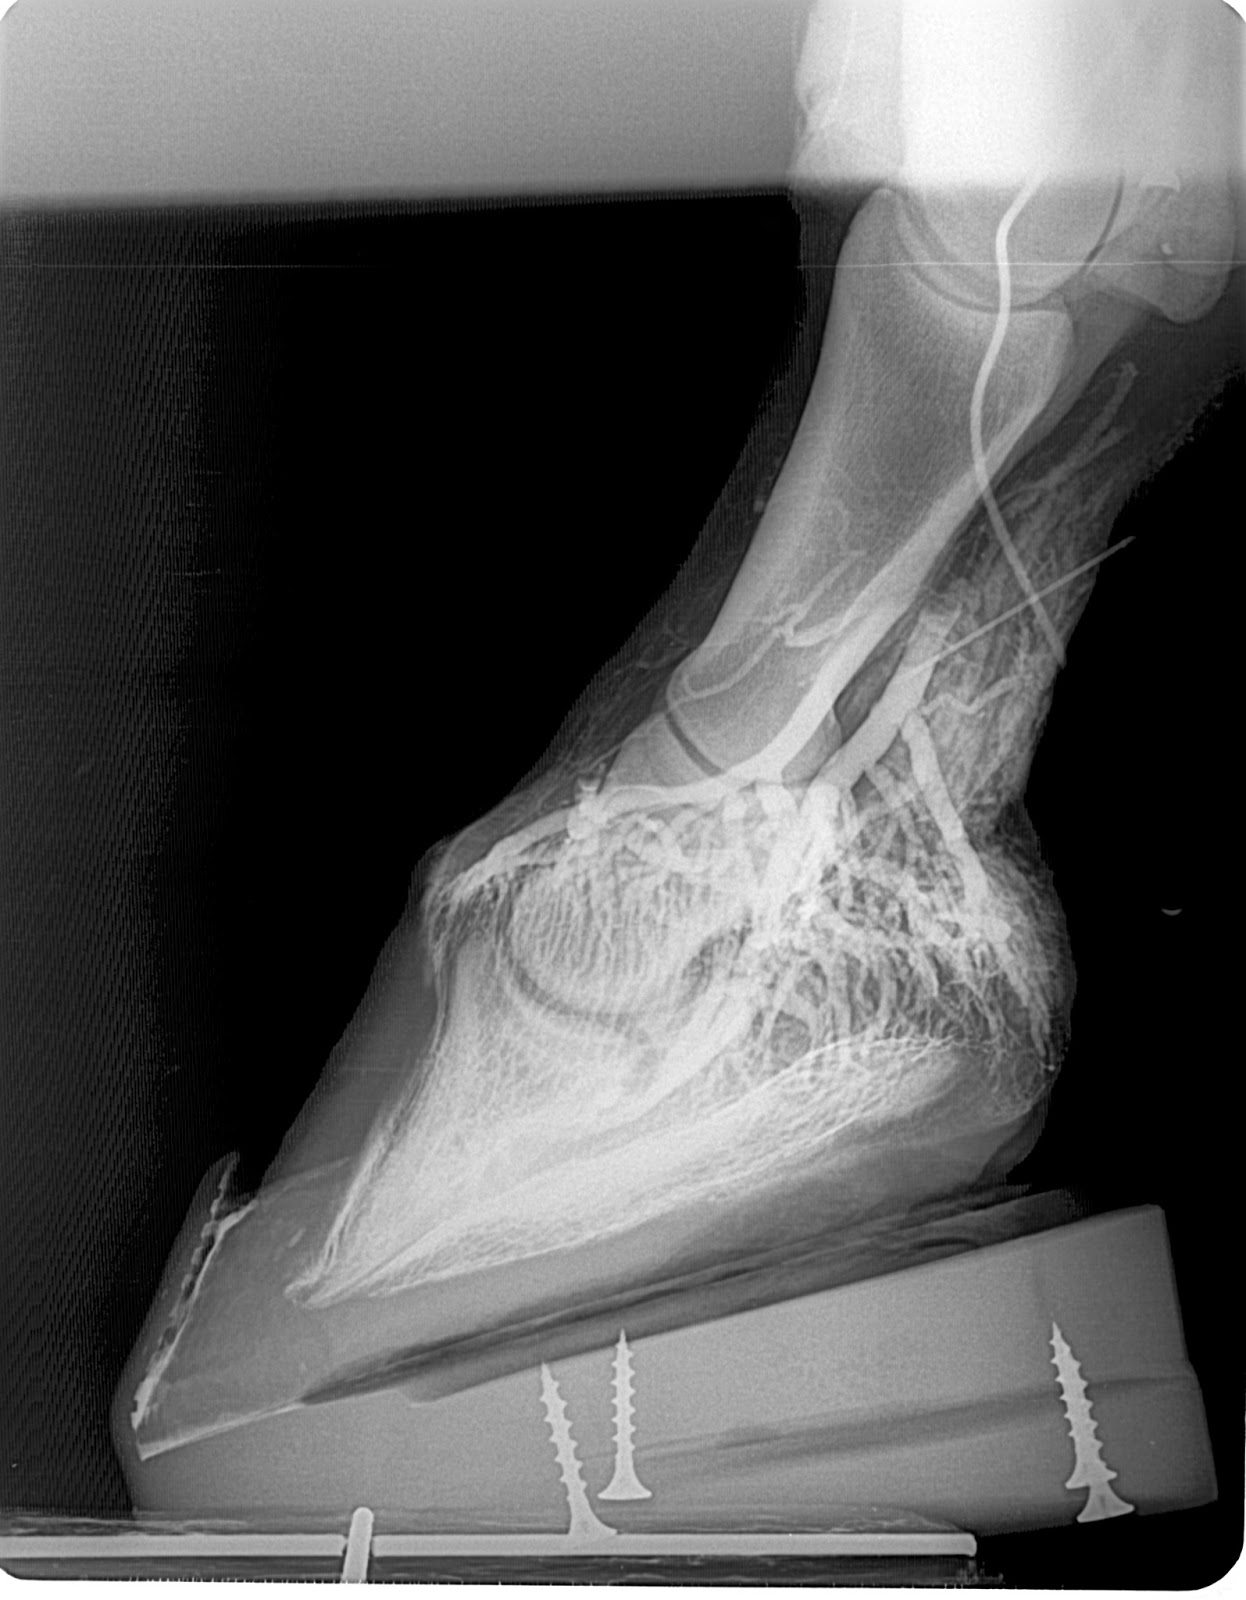

Innovative Equine Podiatry Acute laminitis case showing the value of

XRays of Laminitis How to Detect Laminitis in Horses Laminitis Episode Causes in horses include carbohydrate overload, excess weight bearing, and endotoxemia. The hallmark clinical sign is severe lameness with bounding digital pulses. In severe cases, it can progress to founder, in which the hoof and. Laminitis is a common, extremely painful and frequently recurrent condition in horses, ponies and donkeys. This condition affects the tissues. Laminitis causes the sensitive laminae. Laminitis Episode.

From innovativeequinepodiatry.blogspot.com

Innovative Equine Podiatry Acute laminitis case showing the value of Laminitis Episode P3 rotation or sinking can result from laminar separation in the most severe cases, and it is. Laminitis is inflammation and damage of the tissue between the hoof and the underlying coffin bone. Causes in horses include carbohydrate overload, excess weight bearing, and endotoxemia. This condition affects the tissues. Laminitis is the inflammation and subsequent separation of the laminae of. Laminitis Episode.